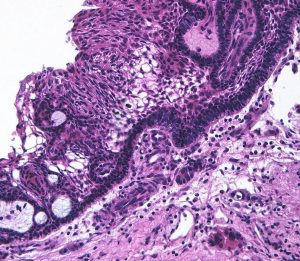

摘出した骨化片の病理像です。成熟した骨組織 mature boneです。

adamantinomatous typeです。mature boneの端には破骨巨細胞が多数見られます。